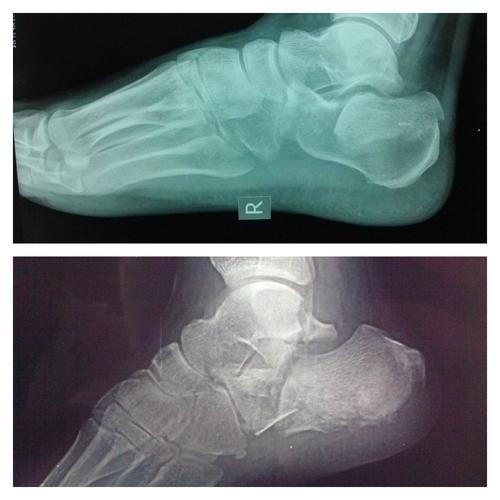

术前跟骨侧轴位片

男42岁,跟骨骨折